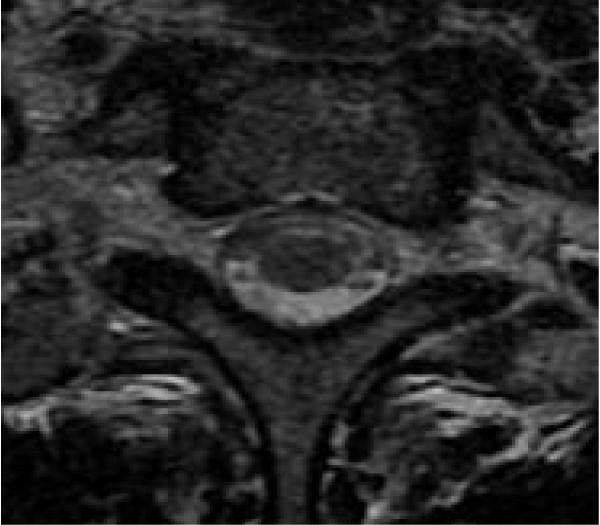

We present a case of cobalamin deficiency in a 29-year-old Moroccan woman who presented with subacute combined degeneration without evidence of anemia or macrocytosis. Magnetic resonance imaging of the spinal cord demonstrated abnormal hyperintense signal changes on T2-weighted imaging of the posterior and lateral columns from the medulla oblongata to the thoracic spine. A diagnosis of subacute combined degeneration of the spinal cord was considered and confirmed by low serum cobalamin. The patient was treated with vitamin B12 supplements and showed improvement in her clinical symptoms.

我们报告一例29岁摩洛哥女性钴胺素缺乏病例,该患者表现为脊髓亚急性联合变性,无贫血或大细胞症证据。脊髓磁共振成像显示,从延髓到胸椎的后柱和侧柱在T2加权成像上有异常高信号改变。考虑诊断为脊髓亚急性联合变性,并通过低血清钴胺素得到证实。患者接受维生素B12补充治疗,临床症状有所改善。